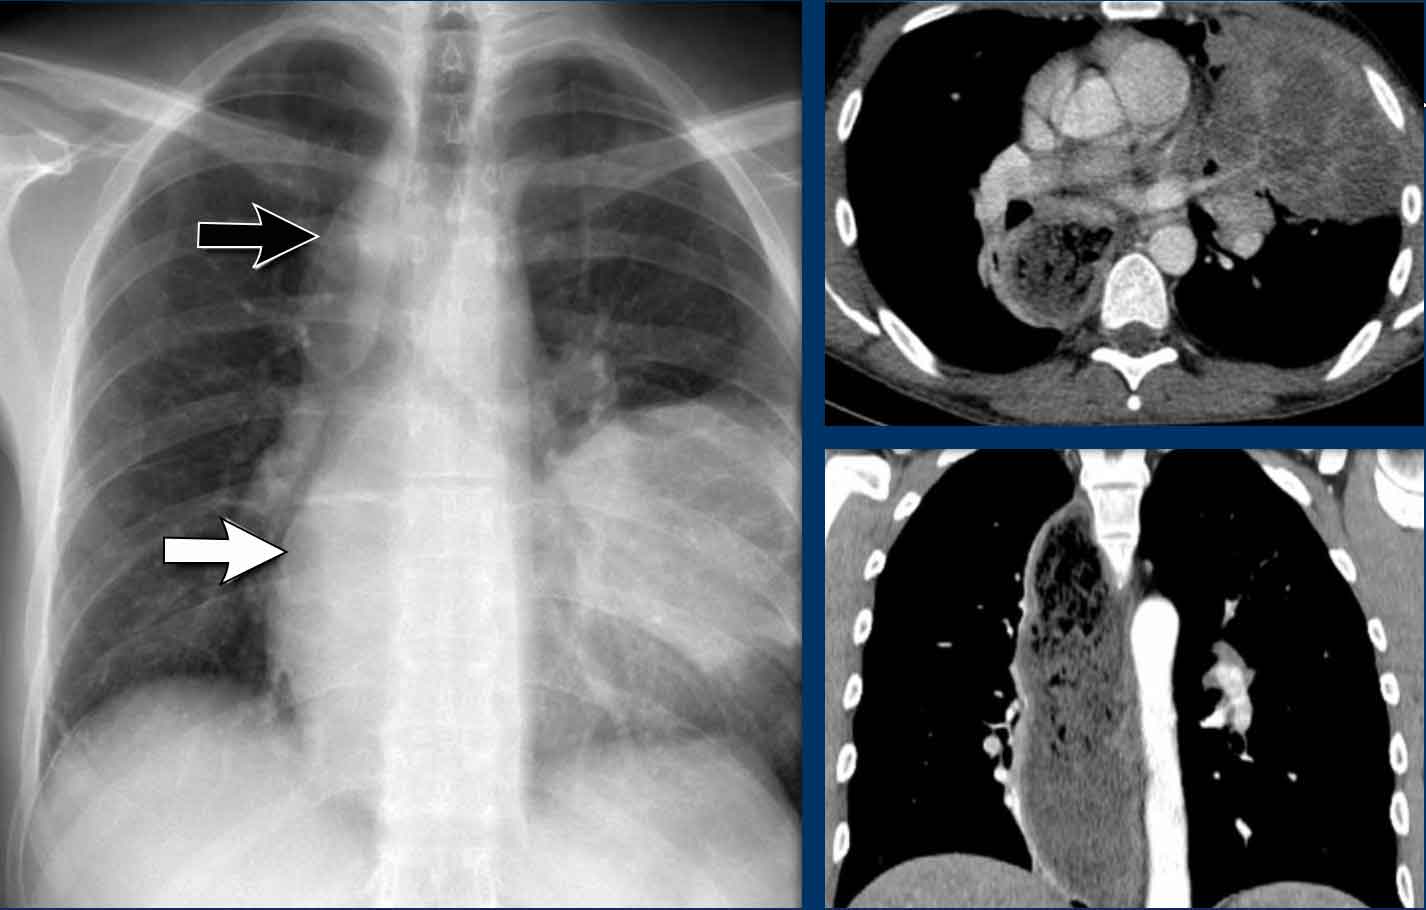

AP window pathology - case 1

Imaging

• PA film shows a mass filling the aortopulmonary window

• Lateral view shows no enlarged pulmonary vessels (black arrow), but a mass projecting into the retrosternal space (white arrow)

Continue with the CT...

CT Imaging

• Mass in the anterior mediastinum is seen.

• Final diagnosis: Hodgkins lymphoma.

AP window mass - case 2

• PA chest X-ray shows a mass occupying the AP window

Continue with the PET-CT...

PET-CT

• PET-CT more clearly defines the extent of nodal metastases

• Final diagnosis: Small cell lung carcinoma